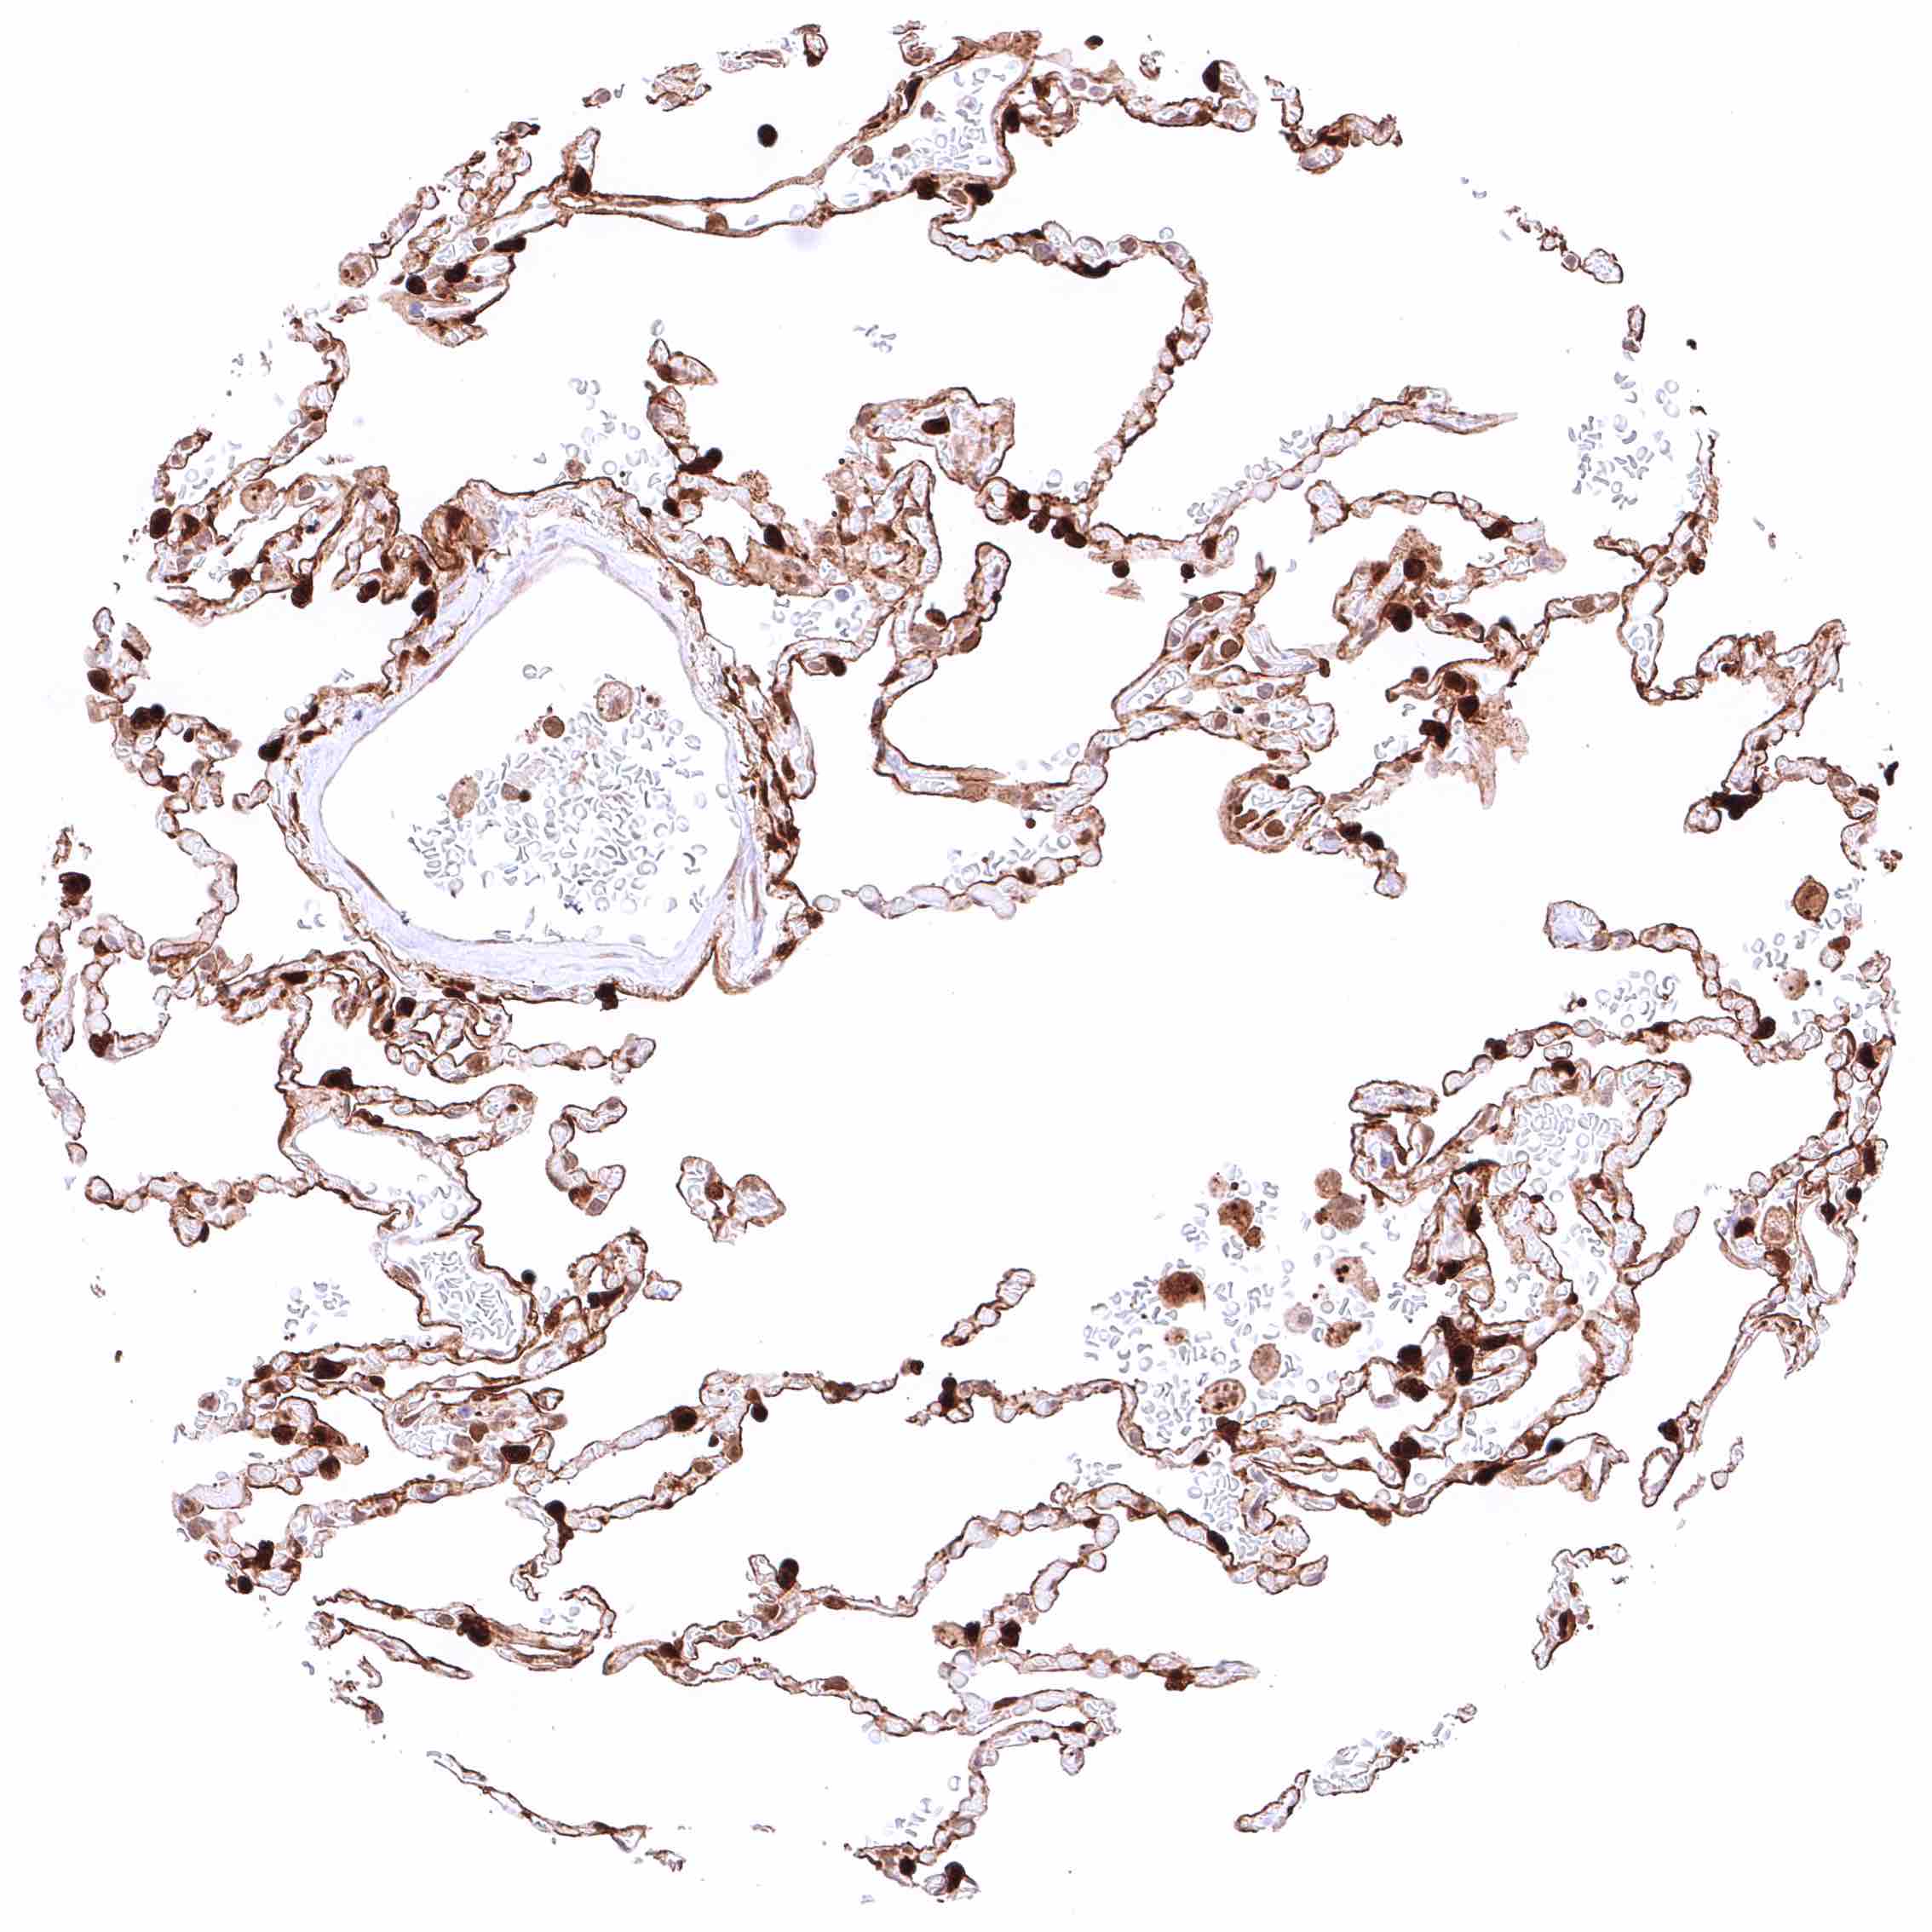

Lung – Moderate, predominantly cytoplasmic positivity of alveolar endothelial cells. Strong, nuclear and cytoplasmic GSTP1 positivity of at least a significant subset of alveolar cells.